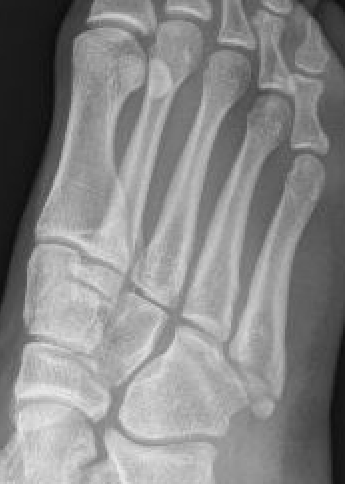

Xray

Zone 2 fractures

Zone 3 Fractures

Progression to nonunion of zone 3 fracture with nonoperative care